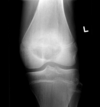

Trauma

Fratura do platô tibial lateral - Schatzker tipo 2 (traço de fratura + depressão do plato lateral).